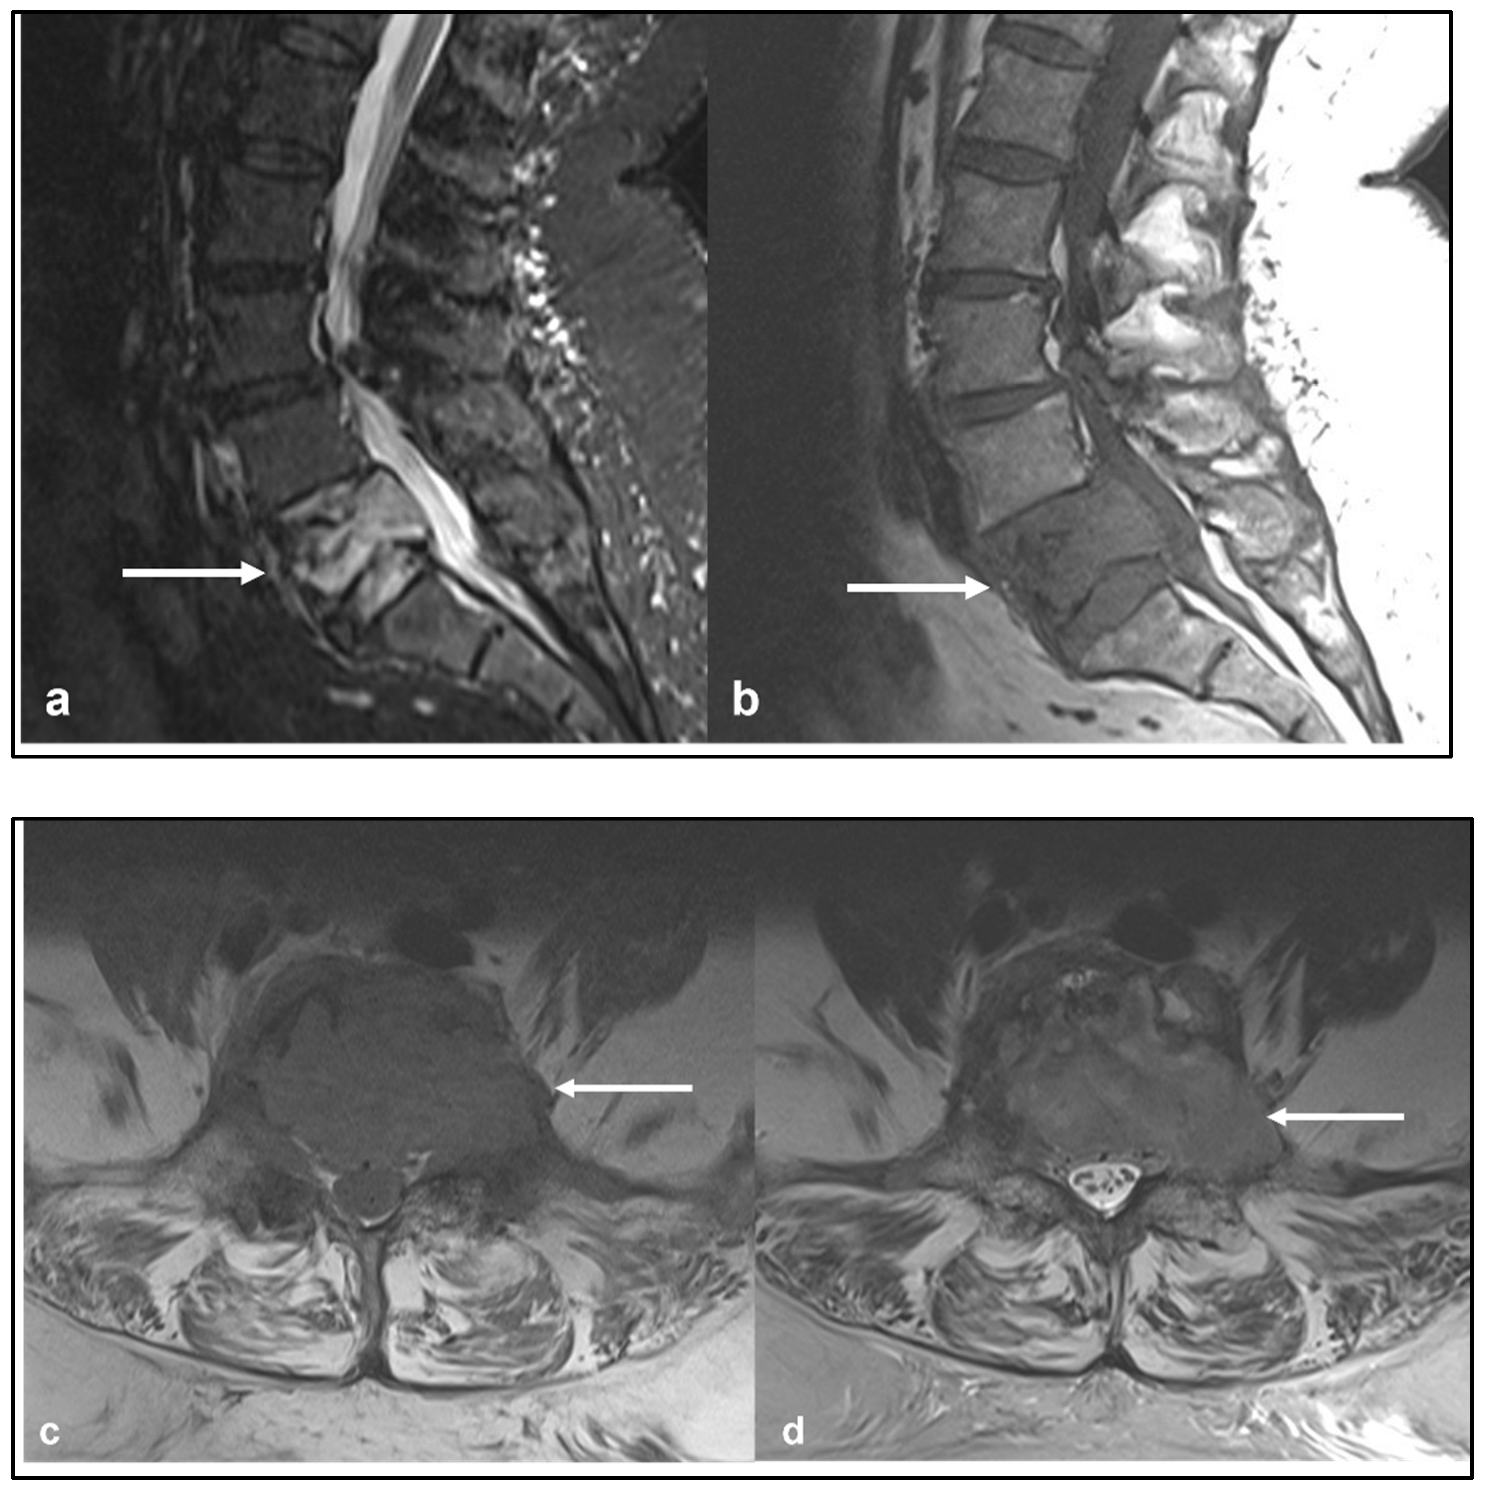

| Chordoma | Low attenuation lytic lesion. | Loculated high T2 signal mass, usually with extra-osseous soft tissue component. High T1 signal due to haemorrhagic and calcified components. |